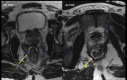

Perianal fistulizing Crohn's disease represents a severe phenotype associated with significant morbidity. Patients with perianal fistulizing disease are more likely to have a severe disease course and have significant reductions in quality of life. Moreover, these patients are at risk for the development of distal rectal and anal cancers. Given the complexity and severity of this patient group, the management of perianal Crohn's disease must be undertaken by a multidisciplinary team. The gastroenterologist and colorectal surgeon play a critical role in the diagnosis and management of perianal fistulizing disease. An examination under anesthesia provides critical information and is an essential part of the work-up of complex perianal fistulas. The radiologist also plays a central role in characterizing anatomy and assessing response to treatment. Several imaging modalities are available for these patients with magnetic resonance imaging as the imaging modality of choice. Perianal disease developing after ileal pouch-anal anastomosis represents a particularly challenging form of fistulizing disease and requires a multidisciplinary clinical and radiologic approach to differentiate surgical complications from recurrent Crohn's disease.